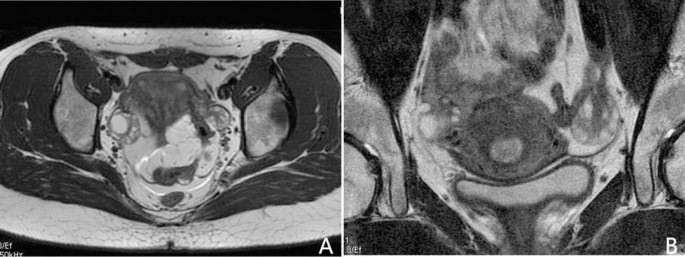

Polycystic ovary syndrome (PCOS), a prevalent reproductive disorder, impacts approximately 5–18% of women during their reproductive years1,2. The Rotterdam criteria3 outline the need to meet at least two specific criteria for diagnosing PCOS: 1) irregular menstruation (IM), 2) hyperandrogenism (HA), and 3) polycystic ovary (PCO). Currently, the assessment of PCO commonly relies on transvaginal ultrasonography (TVUS)4,5. However, the use of TVUS introduces significant variability of follicle count (FC) due to operator dependence and variations in transducer frequencies3,4,5,6. Additionally, TVUS is generally contraindicated in patients with no sexual history7,8,9. Consequently, ovarian MRI has emerged as a recommended alternative. Nonetheless, the depiction of follicles on traditional fast spin-echo (FSE) T2-weighted MR images continues to be compromised by motion artifacts or inadequate spatial resolution (Fig. 1), thereby reducing the repeatability of follicle counting10,11. As a result, there is an urgent requirement for motion-insensitive high-resolution MR images to enhance the repeatability of follicle counting.

Current challenges in follicle counting using traditional fast spin-echo T2-weighted MR imaging. Panel (A) shows the full field of view image, which offers relatively high temporal resolution. However, its low spatial resolution makes follicle counting challenging. In contrast, panel (B) presents a small field of view image with higher spatial resolution, but it is prone to noise and motion artifacts due to its lower temporal resolution, which limits accurate follicle counting.